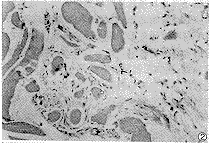

术后30 d,甲组导管周围组织局部炎症反应明显,大量肉芽组织形成。血管明显扩张,充血反应明显,管腔内大量红细胞集聚。局部组织破坏较明显,已有纤维组织增生,浸润的白细胞以中性粒细胞为主,少量巨噬细胞及淋巴细胞,可见有导管的降解颗粒被吞噬现象。(见图1,2)

图1 甲组(术后30 d),局部组织破坏较明显,大量白细胞浸润(HE×300)

图2 甲组(术后30 d),图片正中为P(LA-TMC)导管降解颗粒被巨噬细胞吞噬现象(HE×600)

术后60 d和90 d,乙组和丙组导管周围组织炎症反应呈典型慢性期改变,以纤维组织增生和组织修复为主。局部组织见大量成纤维细胞增生,并已形成瘢痕组织来充填修复破坏区的组织细胞,集聚的白细胞以单核巨噬细胞为主,有大量的导管降解颗粒被吞噬现象。(见图3~6)

图3 乙组(术后60 d),大量肉芽组织增生,炎性细胞浸润,中央为一巨噬细胞浸润(HE×300)

图4 乙组(术后60 d),增生的肌纤维组织中,见一巨噬细胞吞噬降解异物现象(HE×600)

图5 丙组(术后90 d),呈慢性炎症期改变,肉芽组织增生并已瘢痕化(HE×300)

图6 丙组(术后90 d),局部组织有大量P(LA-TMC)导管降解颗粒沉着、被吞噬现象(HE×300)